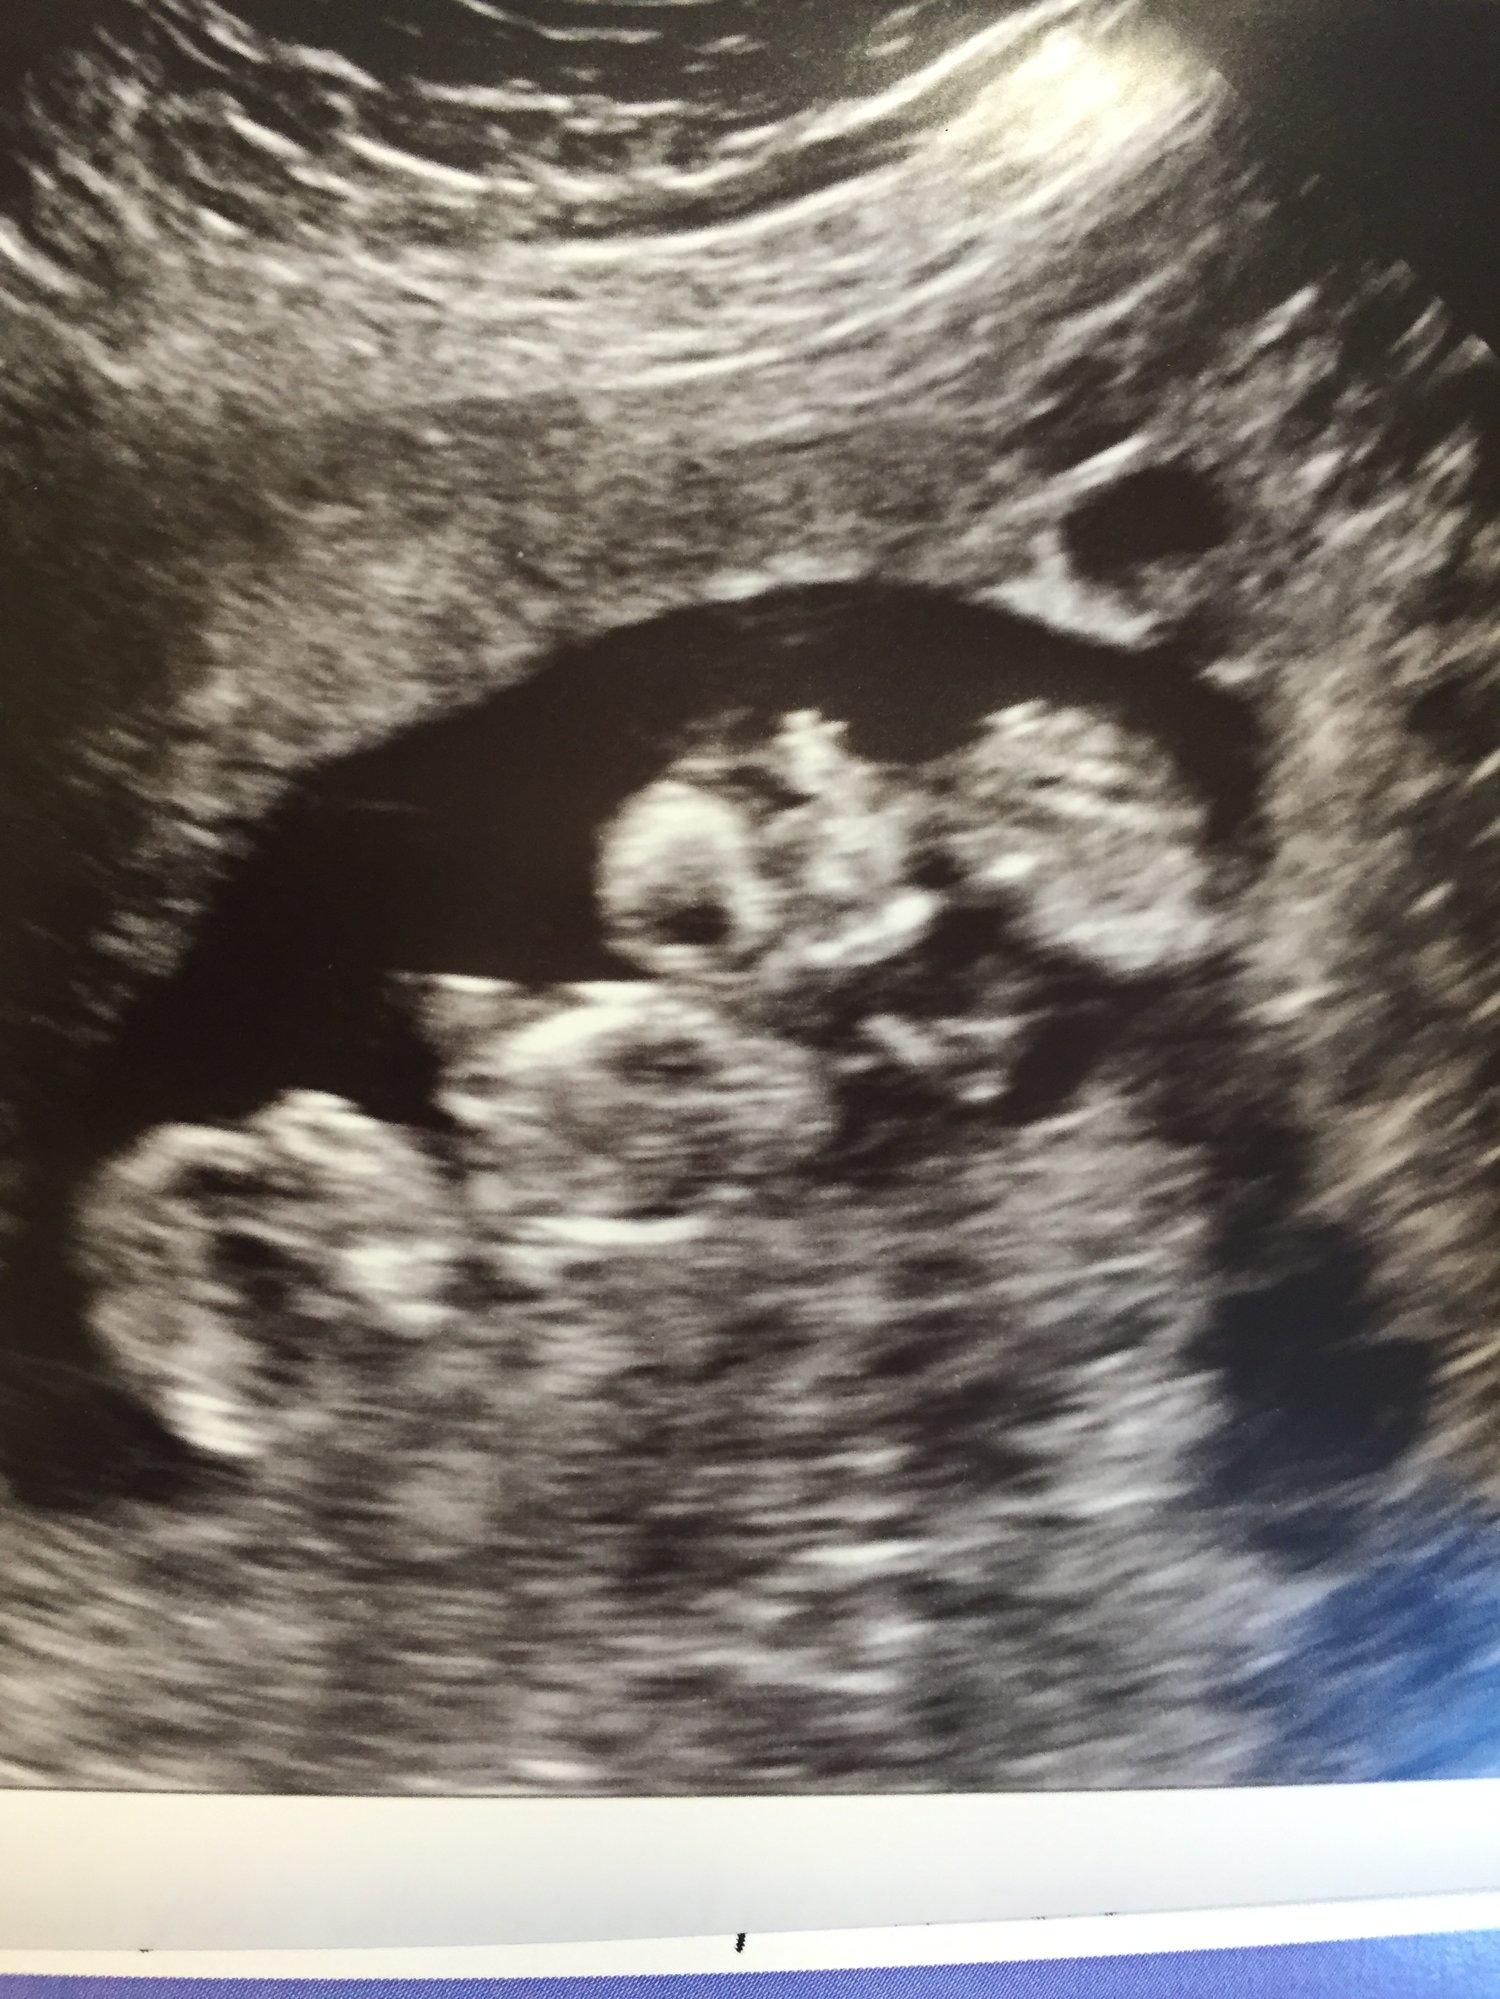

• @breezybee hooray for a good scan!! they are so adorable snuggling together!!

• @breezybee Woooo! @wabash15 took the words right out of my mouth--they look so cozy cuddled up together!